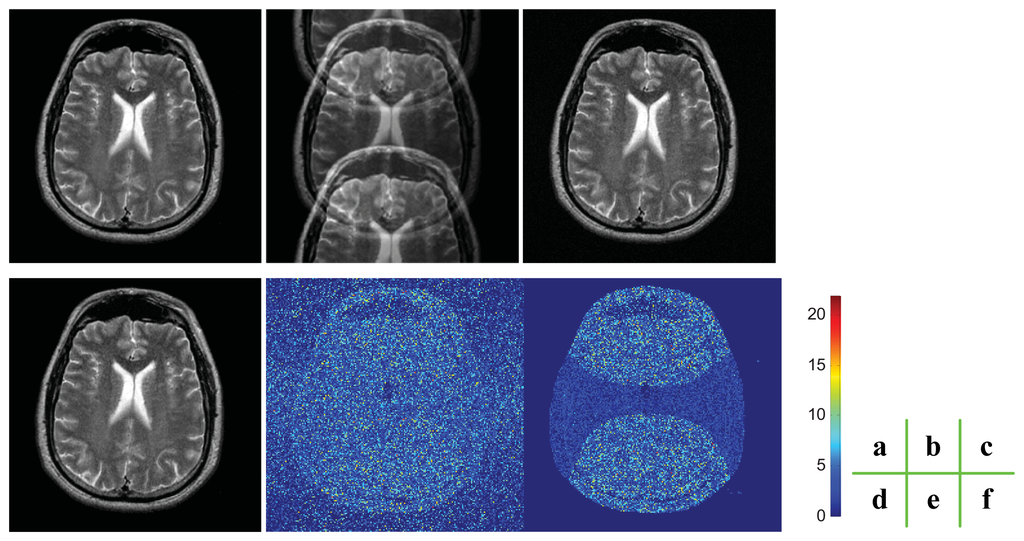

We compared our proposed ROS-based reconstruction method with traditional ROS-based correction method. We first used a fully sampled T2 weighted brain MRI image as a reference data set, undersampled the data with an acceleration rate of 2, applied the aforementioned two methods to reconstruct the images from the undersampled data, and compared the results of the two methods using mean absolute error (MAE) and mean square errors (MSE), which were calculated against the ground truth. To facilitate fair comparison, we calculated MAEs and MSEs on the ROS instead of the whole FOV. In order to assess the performance of sensitivity map estimation, we added Gaussian noise of zero mean and 10−4 variance, which indicates the pixels in the image will have a fluctuation of in their gray intensity values.

Figure 6 indicates that the noise influenced the estimation of sensitivity maps as the artifacts near the center of the brain. The detailed errors indicate that the MAE and MSE of our method are 1.6988 and 9.4573, respectively, while the MAE and MSE of ROS-based correction method 2.0162 and 11.2656, respectively. The results render a reduction of 15.07% for MAE and a reduction of 16.05% for MSE by the proposed method. The errors are calculated on the FOV area, not including the background.

The reason why our ROS-based reconstruction method can achieve less error leans on the H-shape area in Figure 6(f). We know a priori that the corresponding pixels of “H” area should be zero, and the pixels are recovered in pairs. Therefore, we can get a higher signal-to-noise ratio on the H-shape area due to the a priori information.